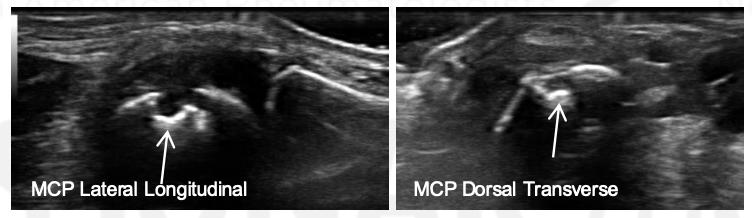

What is 1 and 2?

CPPD at the MCP

What is 3?

This is the interface sign in a normal MCP

What is the arrow pointing to?

CPPD, this is the pseudo double contour sign

What view is this? What is the arrow?

DIP, tophus

MCP; Gout